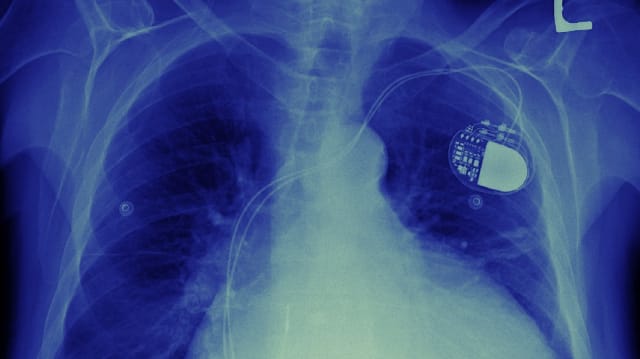

150 Millionen Franken pro Jahr: Etwa so viel bezahlt die öffentliche Gesundheitsversicherung Medicare jedes Jahr für den Austausch von defekten Herz-Implantaten. Oder anders gesagt: Solche Geräte versagen jedes Jahr bei 7'000 bis 8'000 Patienten.

Zu diesem Schluss kommt ein neuer Bericht des amerikanischen Gesundheitsministeriums. Insgesamt sieben Typen von Herzgeräten sorgten in den letzten Jahren für massenhaften Austauschbedarf.

Der Bericht überprüfte solche Eingriffe im Zeitraum von 2005 bis 2014, also über zehn Jahre; und er kam zum Schluss, dass sich die Versicherungs-Kosten dafür auf 1,5 Milliarden Dollar summierten. Hinzu kamen weitere 140 Millionen, welche die Patienten selber auf die eine oder andere Weise beitragen mussten.

Insgesamt sieben Geräte von drei Herstellern hätten eine höhere Fehleranfälligkeit aufgewiesen, meldet der Generalinspekteur des Ministeriums weiter – ohne aber anzugeben, um welche Produkte beziehungsweise Marken es sich handelte.

In die Berechnungen einbezogen wurden jedenfalls nur Herzschrittmacher oder Defibrillatoren, die nachweisbar vorzeitig ausstiegen – oder die vom Hersteller in einer Rückruf-Aktion kassiert werden mussten.